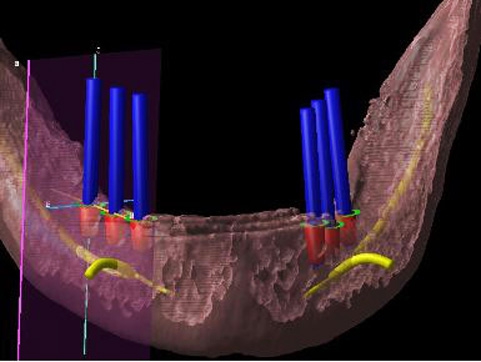

インプラント義歯 ミニインプラント症例

術前術前主訴-総入れ歯の安定が悪い 即時加重可能のミニインプラント使用した。 術前レントゲン術前レントゲン術前レントゲン CT撮影から3次元骨モデルを作成CT撮影から3次元骨モデルを作成CT撮影から3次元骨モデルを作成し埋入位置の確認 フィクスチャーを浸潤麻酔下で埋入フィクスチャーを浸潤麻酔下で埋入。歯茎を切らないので患者さんも非常に楽

4本埋入終了4本埋入終了4本埋入終了(このシステムは4本が絶対条件) 義歯の調整義歯の調整当日に義歯の調整に取りかかる。裏側より義歯をくりぬき維持部のカバー(ハウジング)を義歯の内面に埋め込む step1 義歯の調整義歯の調整当日に義歯の調整に取りかかる。裏側より義歯をくりぬき維持部のカバー(ハウジング)を義歯の内面に埋め込む step2 義歯の調整当日に義歯の調整に取りかかる。裏側より義歯をくりぬき維持部のカバー(ハウジング)を義歯の内面に埋め込む step3